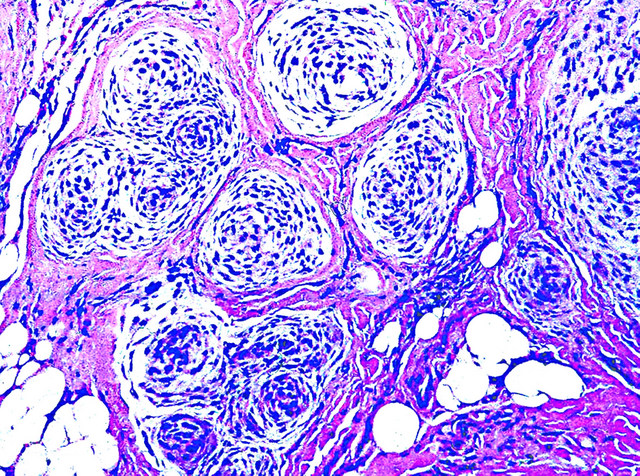

Microscopic (histologic) description

- Cellular, myxoid or mixed subtypes

- Involves dermis or subcutis

- Multinodular mass with myxoid matrix and peripheral fibrosis

- Whorled or focally fascicular patterns of spindled and epithelioid mononuclear cells with abundant cytoplasm, indistinct cell borders

- Margins usually positive; usually occasional multinucleated giant cells

- Variable nuclear atypia

- Median 4 MF / 25 HPF, may have 10+ MF / 25 HPF, may be atypical

Microscopic (histologic) images